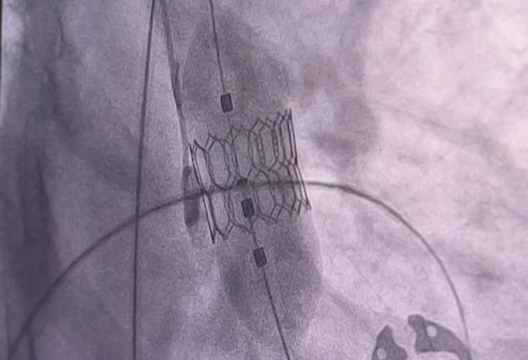

В Центре Сердца UMC прошел мастер-класс по установке нового сердечного клапана Octacor, который имплантируется при аортальном стенозе. Иностранная разработка отличается усовершенствованной конструкцией и используется при проведении TAVI – транскатетерной имплантации аортального клапана. Это малоинвазивная операция по замене аортального клапана, расположенного между левым желудочком сердца и аортой. Процедура выполняется путем введения катетера через бедренную артерию и является оптимальной для пациентов пожилого возраста, которым противопоказано открытое хирургическое вмешательство.

«Открытие учебного центра даст новые возможности для внедрения передовых методов лечения пациентов со структурными патологиями сердца и обучения коллег и молодых специалистов из других регионов и стран. В ходе мастер-класса мы успешно провели 6 процедур по имплантации нового клапана и пригласили на обучение 15 врачей их разных городов Казахстана», – поделился Абдурашид Мусаев, заведующий лабораторией катетеризации Центра Сердца UMC.